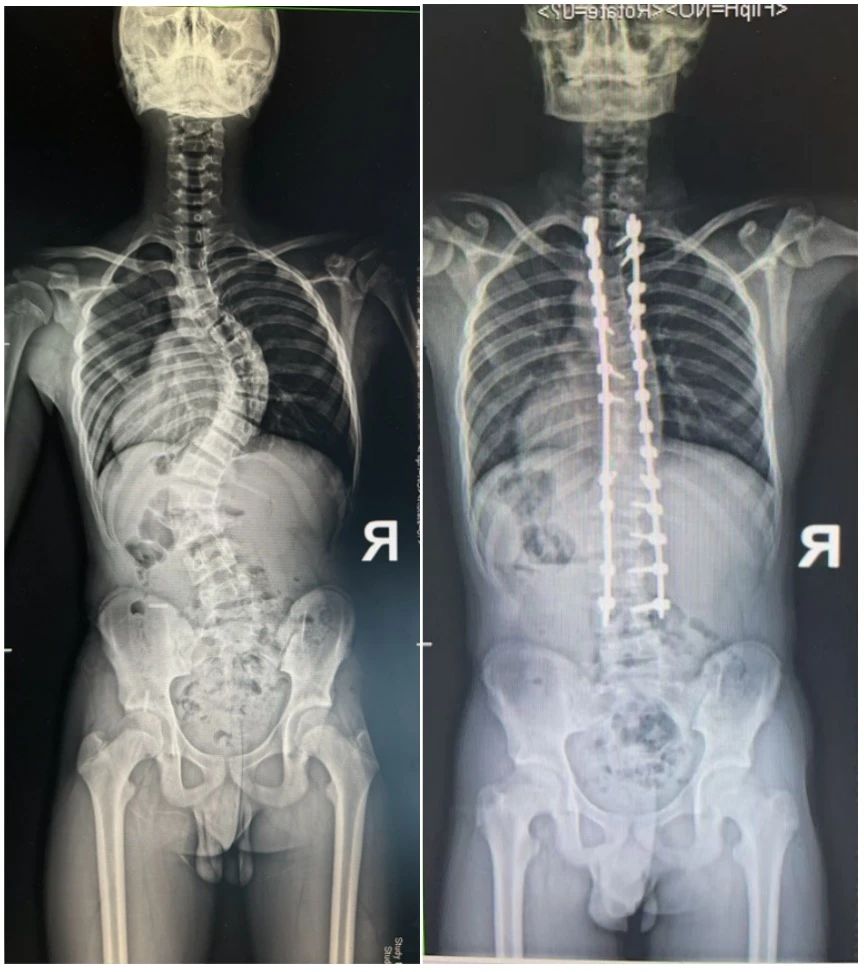

小张自幼便患有特发性脊柱侧弯,随着年龄增长,脊柱侧弯角度逐渐加重,他的脊柱已扭曲成85度的惊人弧度(相当于脊柱弯曲近直角),胸廓变形挤压着心肺,每次呼吸都像在对抗隐形的枷锁,严重影响了他的日常生活和心理健康。传统的保守治疗已无法奏效,手术成为唯一的选择。

"这不是魔术,是医工结合的精准力量。"徐杰教授指着小张的矫形X光片解释:"这些螺钉构成的力学结构,就像给脊柱装上了智能脚手架。"

术前(左)术后(右)对比图